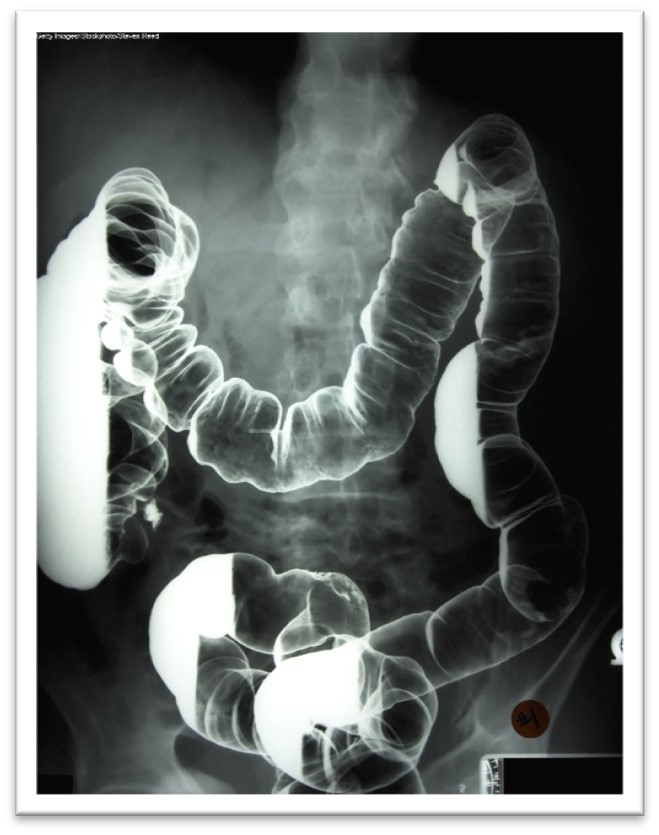

Barium x-rays are used to diagnose underlying pathology within the GI tract, including ulcers, inflammation, tumors, hernias, or strictures. Barium is a white, chalk-like powder mixed with water to create a liquid that is either ingested by the patient or administered via an enema. The barium coats the lining of the GI tract, providing visualization of the walls of the esophagus, stomach, and intestines. This allows radiologists to evaluate these structures' contour, shape, size, and patency to identify any underlying pathology. After the barium is administered, fluoroscopy allows the radiologist to see the movement of the barium through the GI tract. There are three barium x-ray procedures: the barium enema or lower GI series, the barium small-bowel meal, and the barium swallow or upper GI series. Barium x-ray tests are typically performed as an outpatient procedure, and each test's defining features and details are described in Table 4 (Gotfried, 2023; Murphy, 2023a). More information regarding barium is discussed later in this module.

Table 4

Barium X-ray Procedures

Procedure | Description |

Barium enema (lower GI series) |